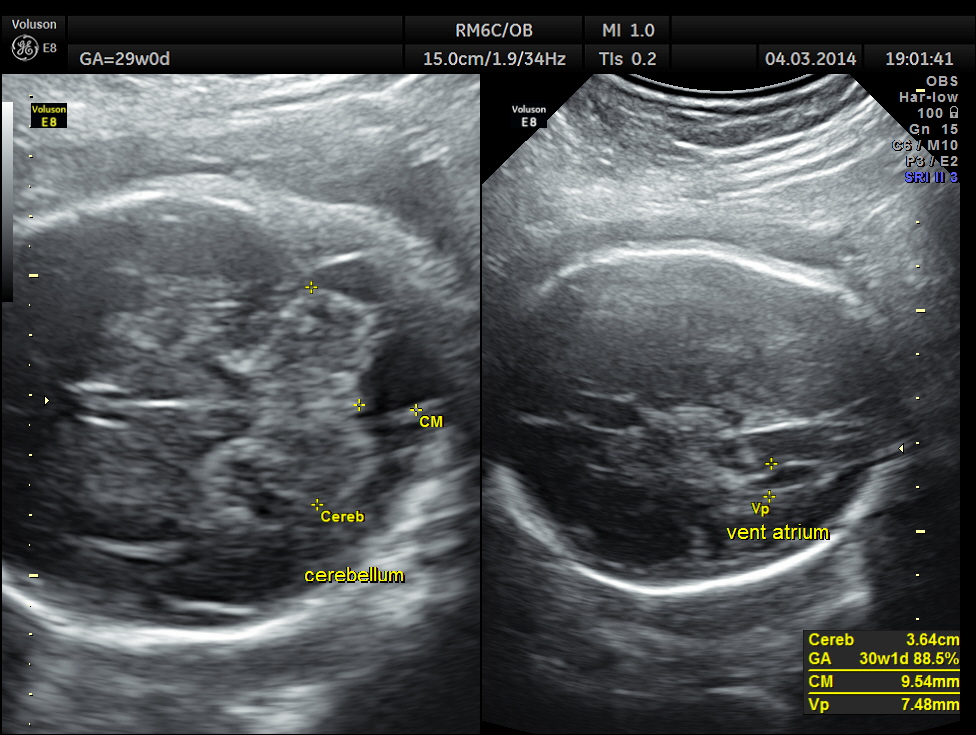

In this patient no other associated anomaly could be made out and so she was re assured ; She came for a review 1 month later.

The unilateral choroid plexus cyst could not be seen now. No other anomaly was made out.